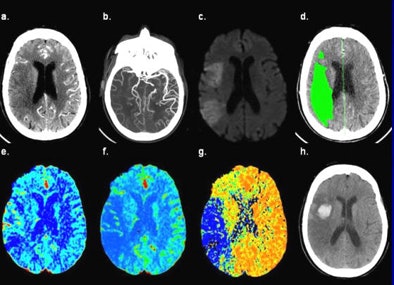

| CT images of an 81-year-old female presenting six hours after the onset of left-sided weakness and right gaze preference; not a candidate for endovascular therapy. (a) 5-mm thick CT angiography source image shows poor tissue opacification of the right middle cerebral artery (MCA) territory. (b) CT angiography maximum intensity projection image shows proximal right MCA occlusion with poor collateralization. (c) DWI-MRI shows right MCA territory infarct core. (d) Thresholded MTT lesion (rMTT > 1.3), with 140 mL total volume. (e) CBV map shows relative hyperemia (increased blood volume) of the cortical right MCA territory. (f) CBF map shows decreased flow of the right MCA territory, corresponding to the DWI lesion. (g) MTT map shows corresponding area of prolonged transit time in the right MCA territory, mean rMTT = 4.3. (h) Twenty-four hour follow-up noncontrast CT shows HT at the anterior right MCA territory. All images courtesy of Leticia Souza, MD, and Shervin Kamalian, MD. |